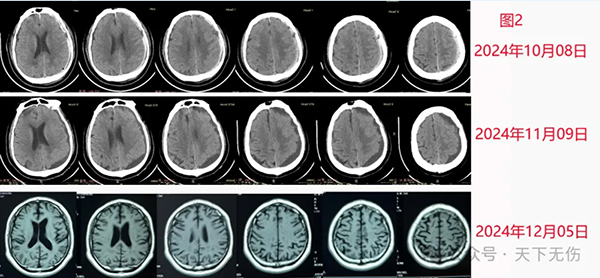

H先生,74岁。10月初发生严重外伤,诊断为脑挫裂伤,颅内积气,左侧硬膜下血肿。因意识尚可,北京某医院没有给他做手术,11月09日复查见血肿液化,但症状逐步加重,出现走路不稳、嗅觉异常和全身异常感觉。非常焦虑。家人陪他到我门诊,他话很少,是家人代叙。因为距离他最近检查的头CT已经接近1个月没有复查了,我说服他去做个头部磁共振。2小时后我看到片子(图2),高兴地恭喜他已经痊愈。我还告诉他和他的家人,脑外科已经无需治疗。追问病史,才得知,他也是在医生建议下自服阿托伐他汀钙,而且服用了43天。得知不必再治疗的消息后,他们开始简直不敢相信,当再次确认后,一家人高兴地带着患者离开,不说话的这位患者,临走时居然也笑着开口向我表达致谢了。

Z女士,62岁,今年6月头部被硬物砸伤,然后就在当地医生建议下开始口服阿托伐他汀钙,但到10月底自觉头晕头闷,在当地确诊为慢性硬膜下血肿。患者焦虑,由儿子陪着从几百里外的河北某地赶到北京找我求诊。同样是因为她的最后影像学资料距离门诊日太过久远,我建议她接受新的检查。快下班时拿到她的最新影像学检查结果,显示老人家的血肿已经大部消失、仅剩一点点残余(图3)。我告诉她,她可以吃药也可以不吃药,已经接近痊愈了。患者和她的儿子听了后也是一脸懵懂,确认后高兴不已,连连向我致谢,说他们也是慕名求诊到我门诊。